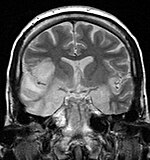

Herpesviral encephalitis and herpesviral meningitis Herpes simplex encephalitis (HSE) is a rare life-threatening condition that is thought to be caused by the transmission of HSV-1 either from the nasal cavity to the brain's temporal lobe or from a peripheral site on the face, along the trigeminal nerve axon, to the brainstem.[17][18][19][20] Despite its low incidence, HSE is the most common sporadic fatal encephalitis worldwide. HSV-2 is the most common cause of Mollaret's meningitis, a type of recurrent viral meningitis.

Hsv encephalitis.jpg